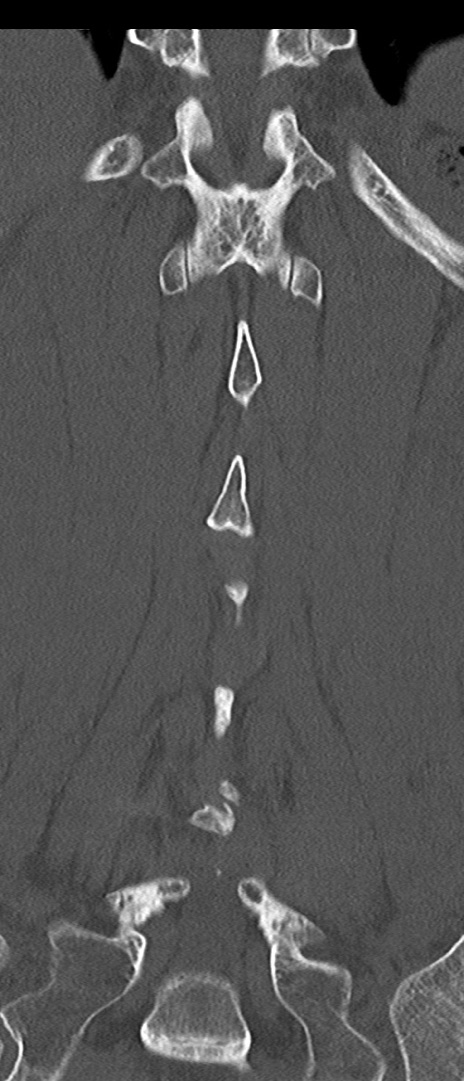

【整形】TIPS症例4 腰椎CT(冠状断像)

腰椎CT